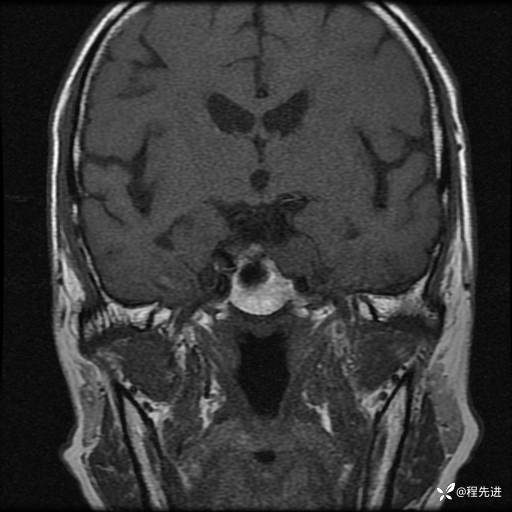

MRI平扫+增强:

T1:

T1增强: